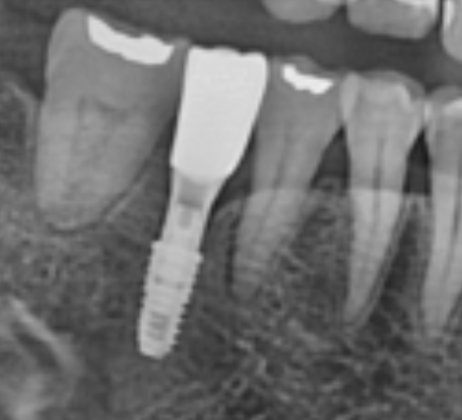

반갑습니다. 치의학 박사 장영준입니다. 임플란트 수술을 앞둔 분이라면, ‘뼈이식’이라는 단어를 한 번쯤은 들어보셨을 것이라고 생각됩니다. 뼈이식은 쉽게 말해 임플란트 픽스쳐(나사)를 심을 때, 잇몸뼈를 더욱 단단하게 보충하기